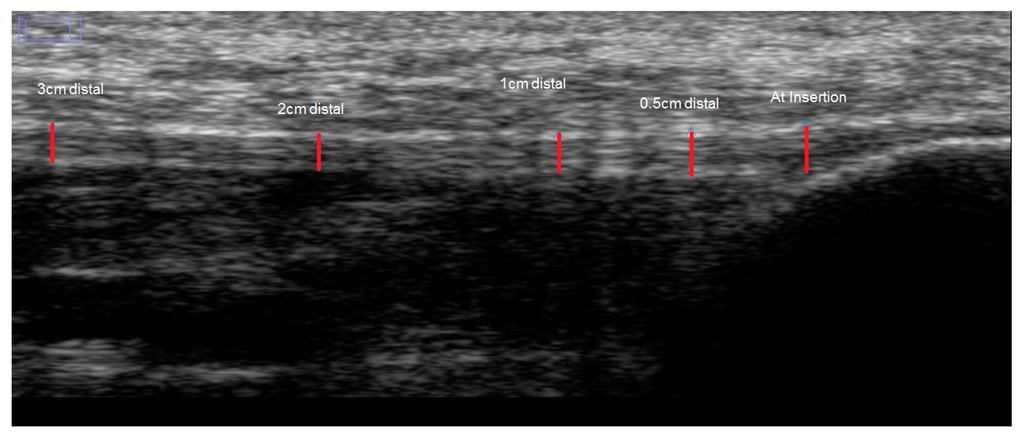

2.2. Test Procedure

2.3. Image Analysis